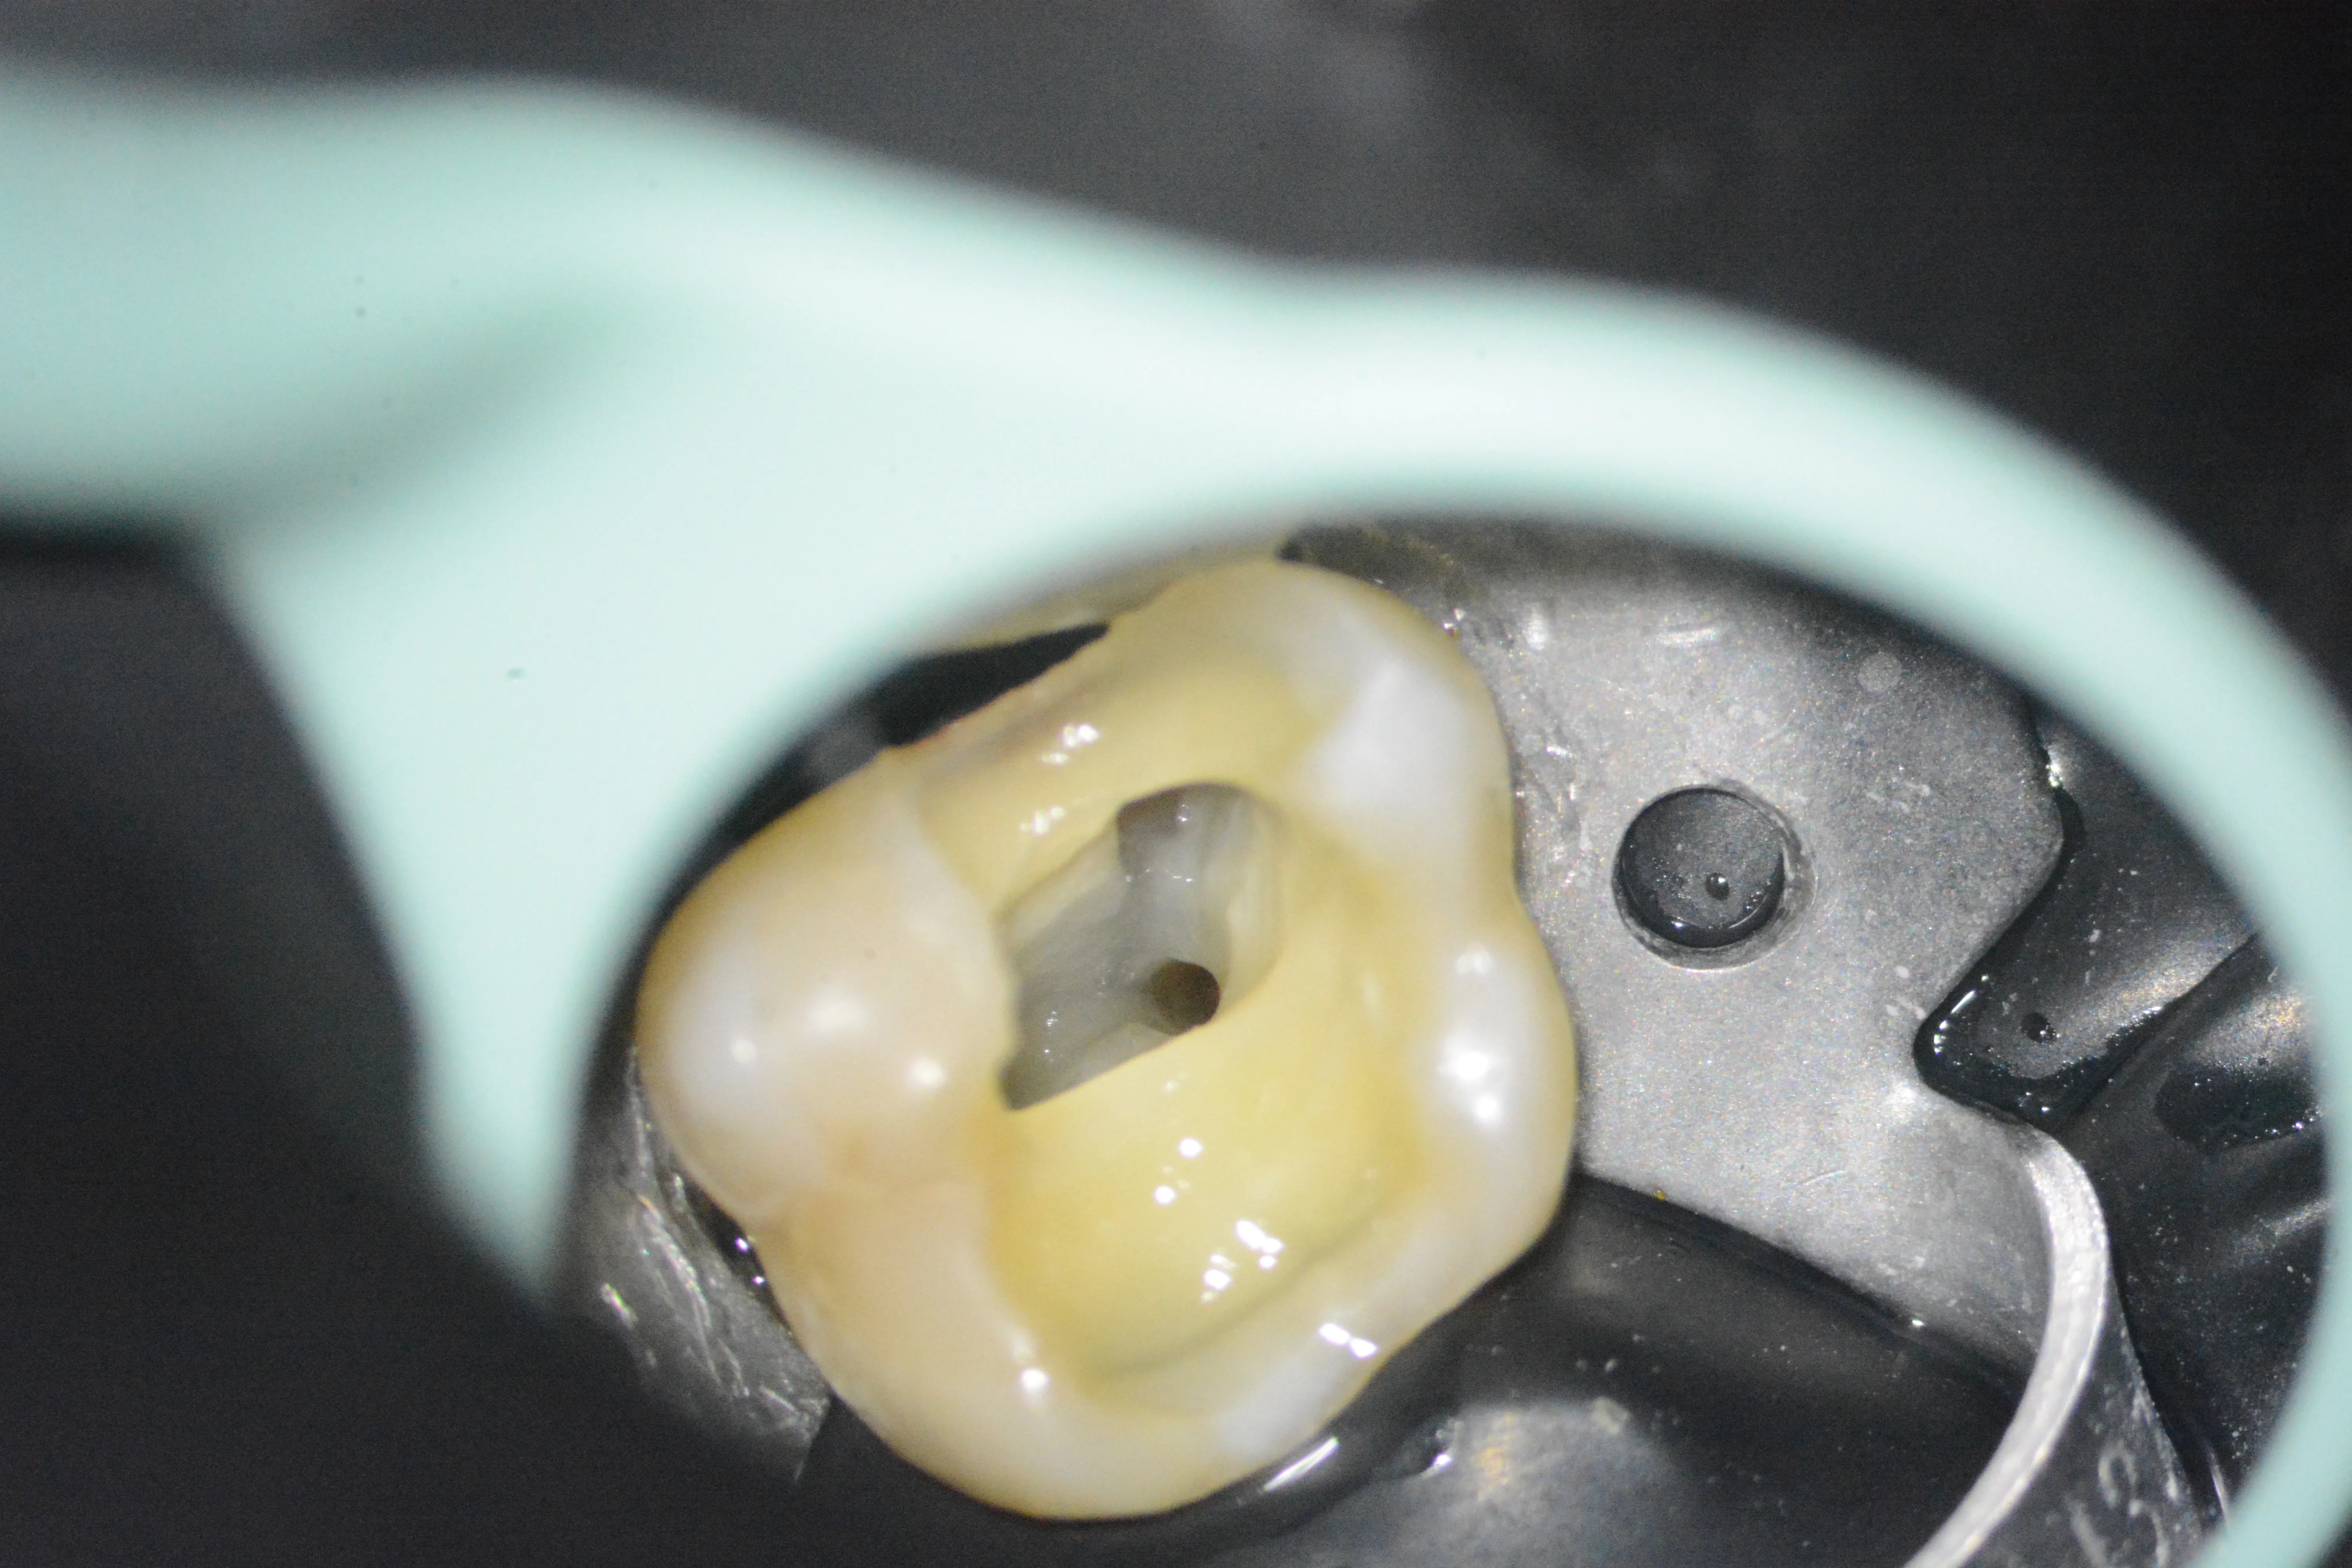

2 – Aspect clinic inițial